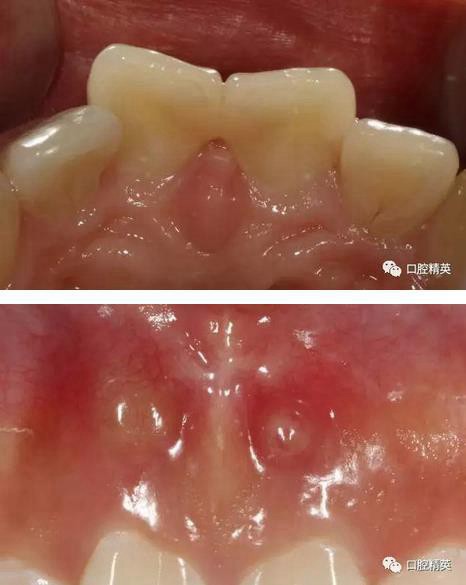

術前檢查

可見兩側(cè)齦緣外形不平整

激光休整牙齦前后

術前,術中,術后對比

有一點不足之處在于齦緣的高低不完全一致,補救辦法同上——激光輕掃